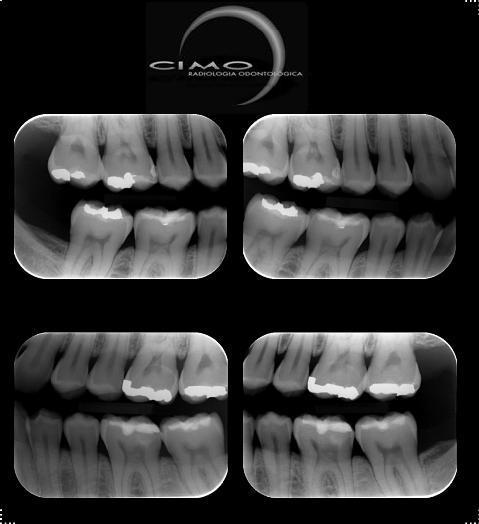

Também chamada de “Bite Wings”, é a técnica de eleição para o diagnóstico de cárie proximal, permitindo também o estudo

de cristas alveolares, verificação da relação cárie-câmara pulpar, adaptação de restauração e peças protéticas e cálculos em

dentes posteriores.

Numa boca adulta são realizadas quatro tomadas radiográficas: pré-molares e molares para cada lado.